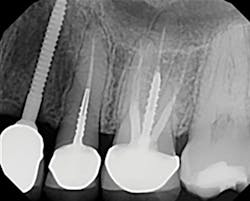

A 32-year-old male presented with a congenitally missing lateral, No. 10. The buccal-lingual dimensions were sufficient for standard implant placement, but the mesial-distal dimensions were 4.56 mm (figures 1a and 1b). The patient had a failing Maryland bridge, both functionally and esthetically (figure 2). He was always told that implants were not an option for him unless he underwent significant orthodontic treatment, and even then, nothing was guaranteed.

By selecting a 2.4 mm Anew implant (Dentatus), we were able to preserve sufficient bone between implant and tooth (1.5 mm), allowing for gingiva, a natural emergence profile, and maintaining the papilla in this highly esthetic area. Gingival recontouring was performed with a diode laser (Epic, Biolase). We had the lab fabricate a surgical guide and an immediate screw-retained provisional restoration for flapless implant placement (figures 3 and 4).

Figure 1a: Pre-op panorex

Figure 1b: Pre-op CT scan

Figure 5: Post-op panorex